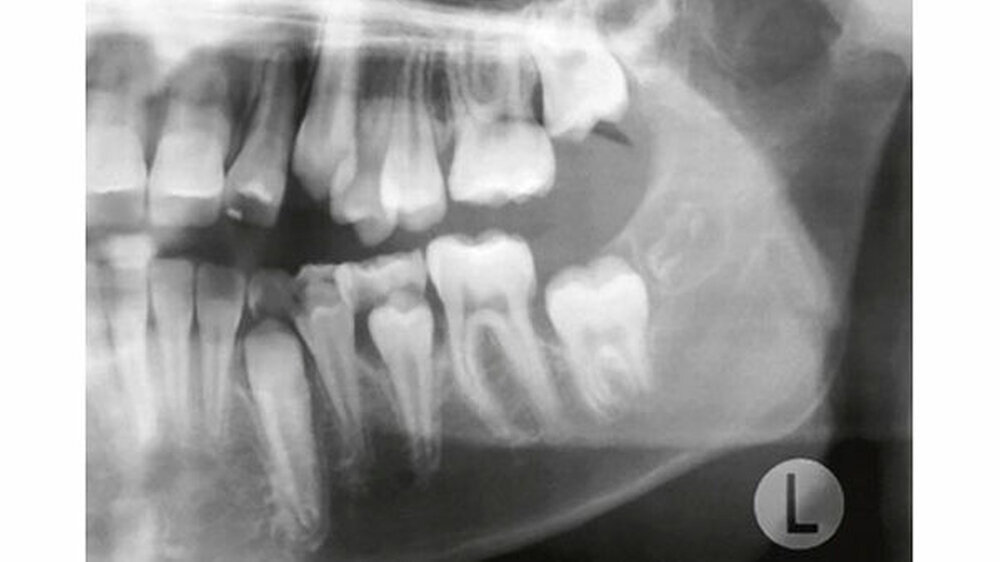

Auf dem mitgelieferten vier Jahre zuvor erstellten Orthopantomogramm (OPT) waren noch keine Hinweise auf das Vorhandensein einer Veränderung regio 32-34 sichtbar (Abbildung 2). Ein Jahr später konnte anhand des OPT bereits eine radioopake Struktur regio 33, 34 festgestellt werden (Abbildung 3). Auf dem aktuellen OPT und digitalen Volumentomogramm (DVT) zeigten sich regio 32-34 lingual multiple, rundliche, unterschiedlich große Radioopazitäten, umgeben von einer radioluzenten Zone.